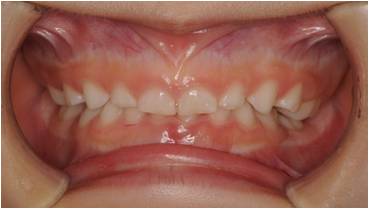

治療後

受け口の小児矯正治療(7歳の女子)の治療前後の写真です。矯正治療によって下顎前突(受け口)と上顎の狭さが改善され、正しい咬合に導かれています。